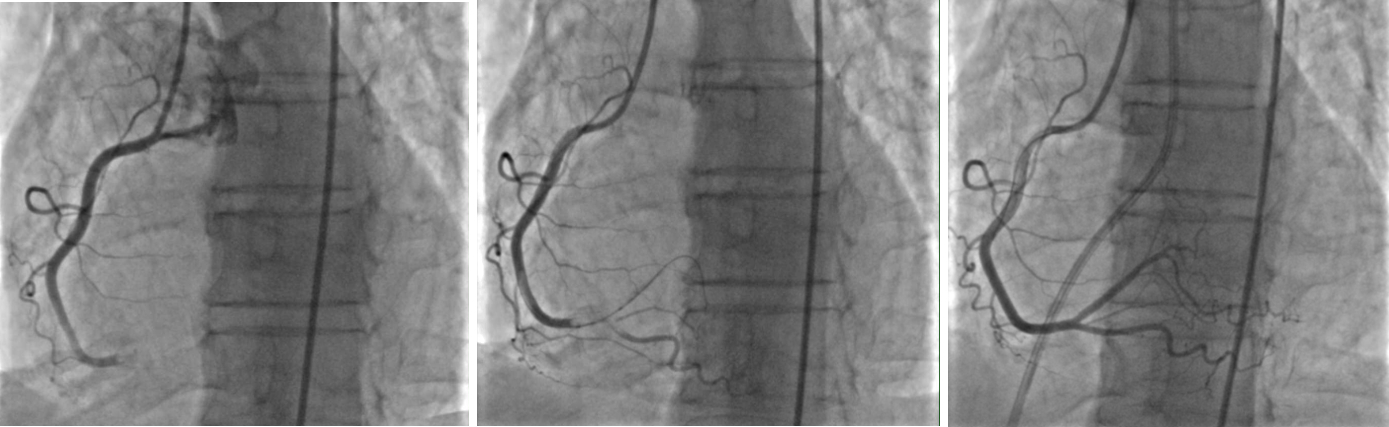

Abstract Body (Do not enter title and authors here): Case Presentation: A 53-year-old woman with a history of recent left patellar fracture and tobacco use presented with sudden-onset chest pain and shortness of breath. ECG showed ST elevations in II, III, and aVF with reciprocal depressions. CT angiography revealed a saddle pulmonary embolism with extensive bilateral emboli and right heart strain. Emergent coronary angiography showed 100% RCA occlusion - from proximal PDA through the AV groove. She was diagnosed with massive, high-risk PE and experienced progression from second- to third-degree AV block, which resolved after revascularization. Percutaneous coronary intervention was performed with successful RCA thrombectomy. She developed cardiogenic shock requiring norepinephrine and milrinone. The shock team placed an intra-aortic balloon pump (IABP). Ultrasound showed a non-occlusive thrombus in the left posterior tibial vein. Transthoracic echocardiogram on the following day of hospitalization showed normal LVEF (60–65%), RV dilation, septal flattening, and severely reduced RV systolic function. A bubble study confirmed a patent foramen ovale with right-to-left shunting. Due to RV wall thinning and elevated pulmonary pressures, the Pulmonary Embolism Response Team recommended IR-guided mechanical thrombectomy. Post-procedure, the patient improved and was weaned off IABP, pressors, and ventilator support. At discharge, she was started on a direct oral anticoagulant. One-month follow-up TTE revealed normalized RV size, mild right atrial dilation, and preserved LVEF.